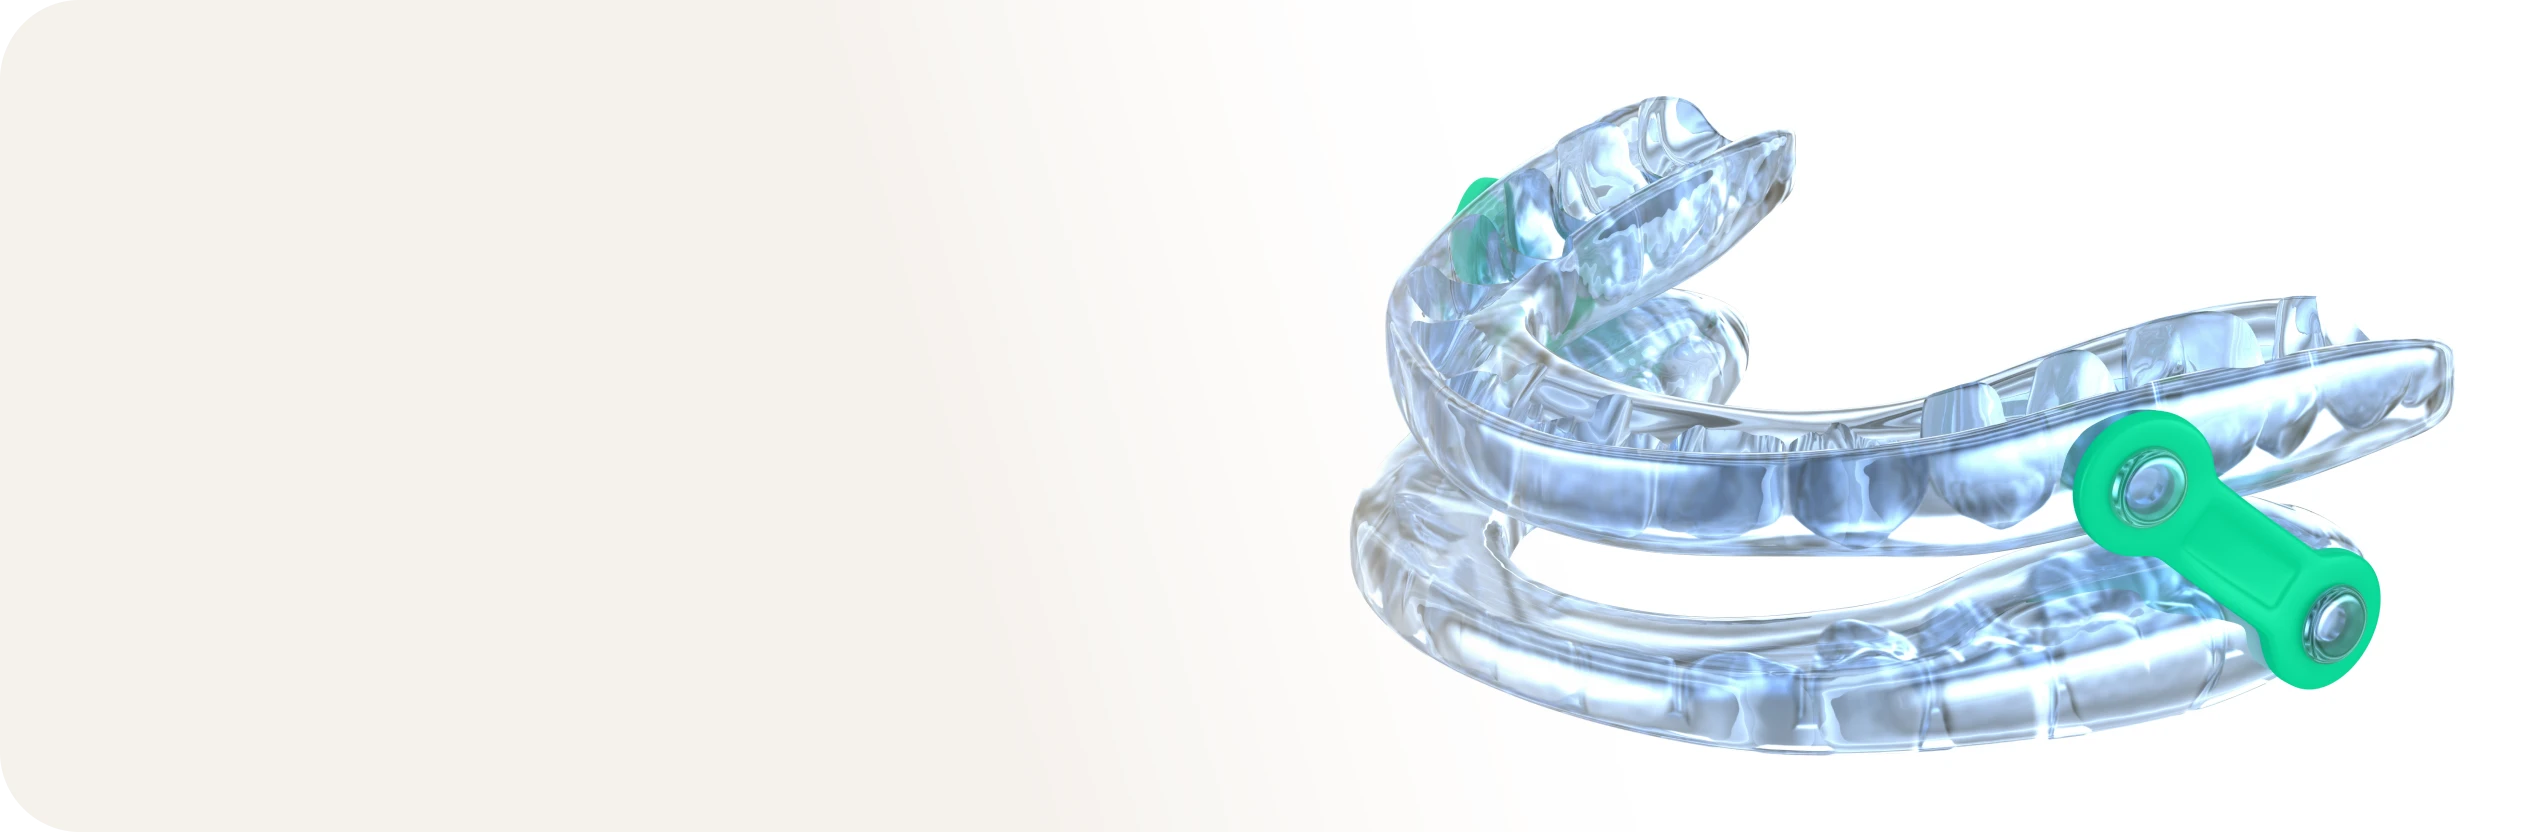

Orthèse d'avancée mandibulaire

Orthèse d'avancée mandibulaire

Une gouttière avancée, ou orthèse d’avancée mandibulaire, est un dispositif personnalisé destiné à traiter le ronflement et l’apnée du sommeil obstructive en maintenant la mâchoire inférieure dans une position avancée. Elle est conçue sur mesure à partir d’empreintes dentaires pour garantir un ajustement confortable et efficace. Son utilisation régulière peut significativement améliorer la qualité du sommeil et diminuer les risques de complications liées aux troubles respiratoires nocturnes.